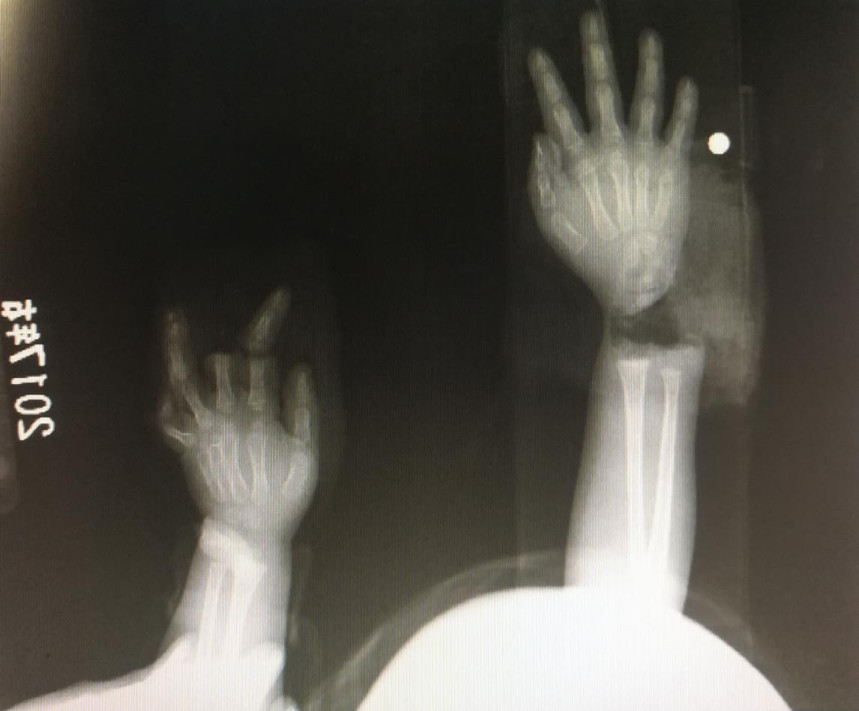

“急診在哪,急診在哪”,伴隨著一聲聲急促的問(wèn)詢,一位年輕女士抱著渾身是血的小孩疾步前往急診室,懷里的小孩在疲憊與疼痛的交織下,時(shí)睡時(shí)醒。鑒于小孩的情況,急診醫(yī)生迅速安排給小孩拍了X光片,影像片結(jié)果顯示小孩左手手腕完全離斷,右手中、食指離斷,距離事發(fā)時(shí)間已經(jīng)3個(gè)多小時(shí),需盡快安排手術(shù)。